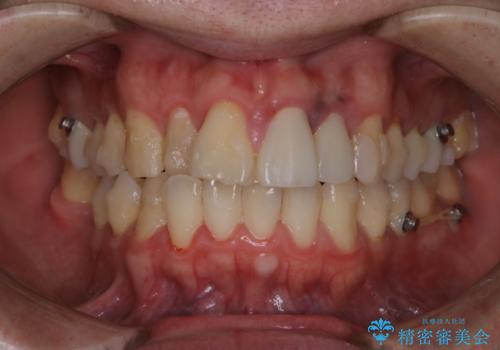

- インビザライン中に着色が気になるとのことでした。PMTC30分コースを行いました。

インビザライン治療中には、歯の表面にアタッチメント(効率的に歯の移動をするもの)を設定します。そのため歯ブラシでは届きにくい細かい部分などに、歯石や着色がついてしまうことがあります。着色などを放置していると、着色なのか、虫歯なのかの判別もしずらく正確にお口の中の状態を診断できません。

矯正治療中も定期的に歯科医院にてPMTCを受けて、お口のケアを行うことをおすすめします。